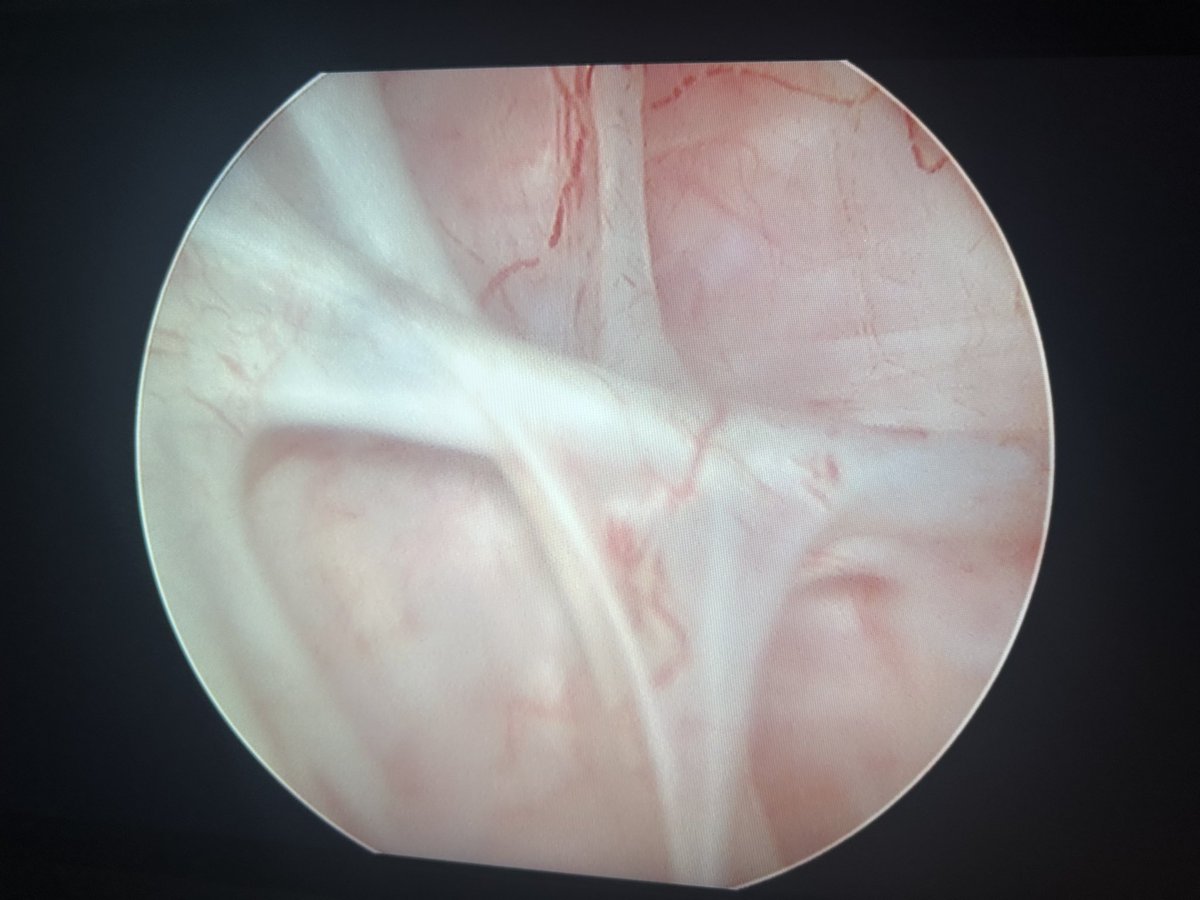

1.5 yo with 9 mm pelvis stone.

During flex URS with PUSEN A 3303 (7,5Fr) + #fiberdust you see this “bubble”. What are your diagnostic thoughts ?